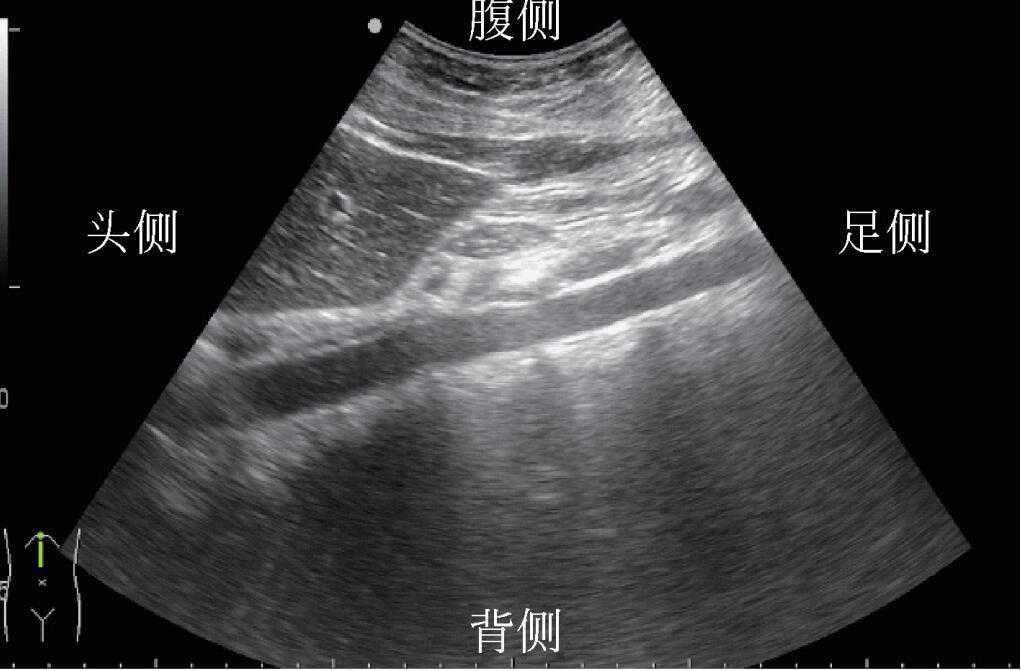

1)探头沿着患者身体长轴方向扫查为纵向或矢状切面。若探头标记指向患者头侧,则在有标记的屏幕侧的结构为患者头侧结构(图5)。

图5探头位置与声像对应关系(纵向)